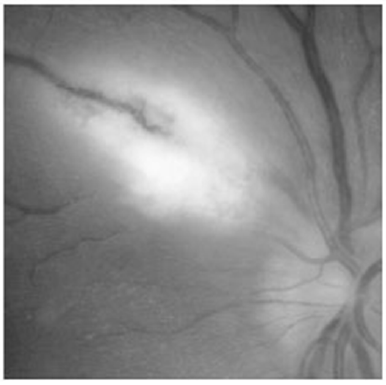

A figura acima mostra um tipo específico de catarata. Ela se caracteriza por ser unilateral (90% dos casos), podendo ter herança autossômica dominante. Considerando essas informações, assinale a alternativa que apresenta o passo da cirurgia que deve ser evitado.